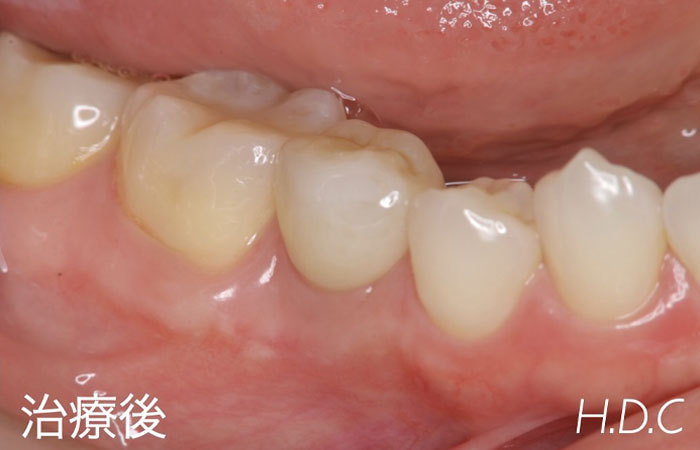

根管治療例③

- 年齢・性別

- 30代 男性

- 主訴

- 右上の前歯の歯肉が腫れた。

- 診断名

- 根尖性歯周炎

- 治療内容

- 根管治療後、コンポジットレジンにて修復治療を行いました。

- 治療期間

- 約3ヶ月

- 治療費用

- 保険診療

- リスク

- 根尖性歯周炎の再発、歯根破折、コンポジットレジンの破折など